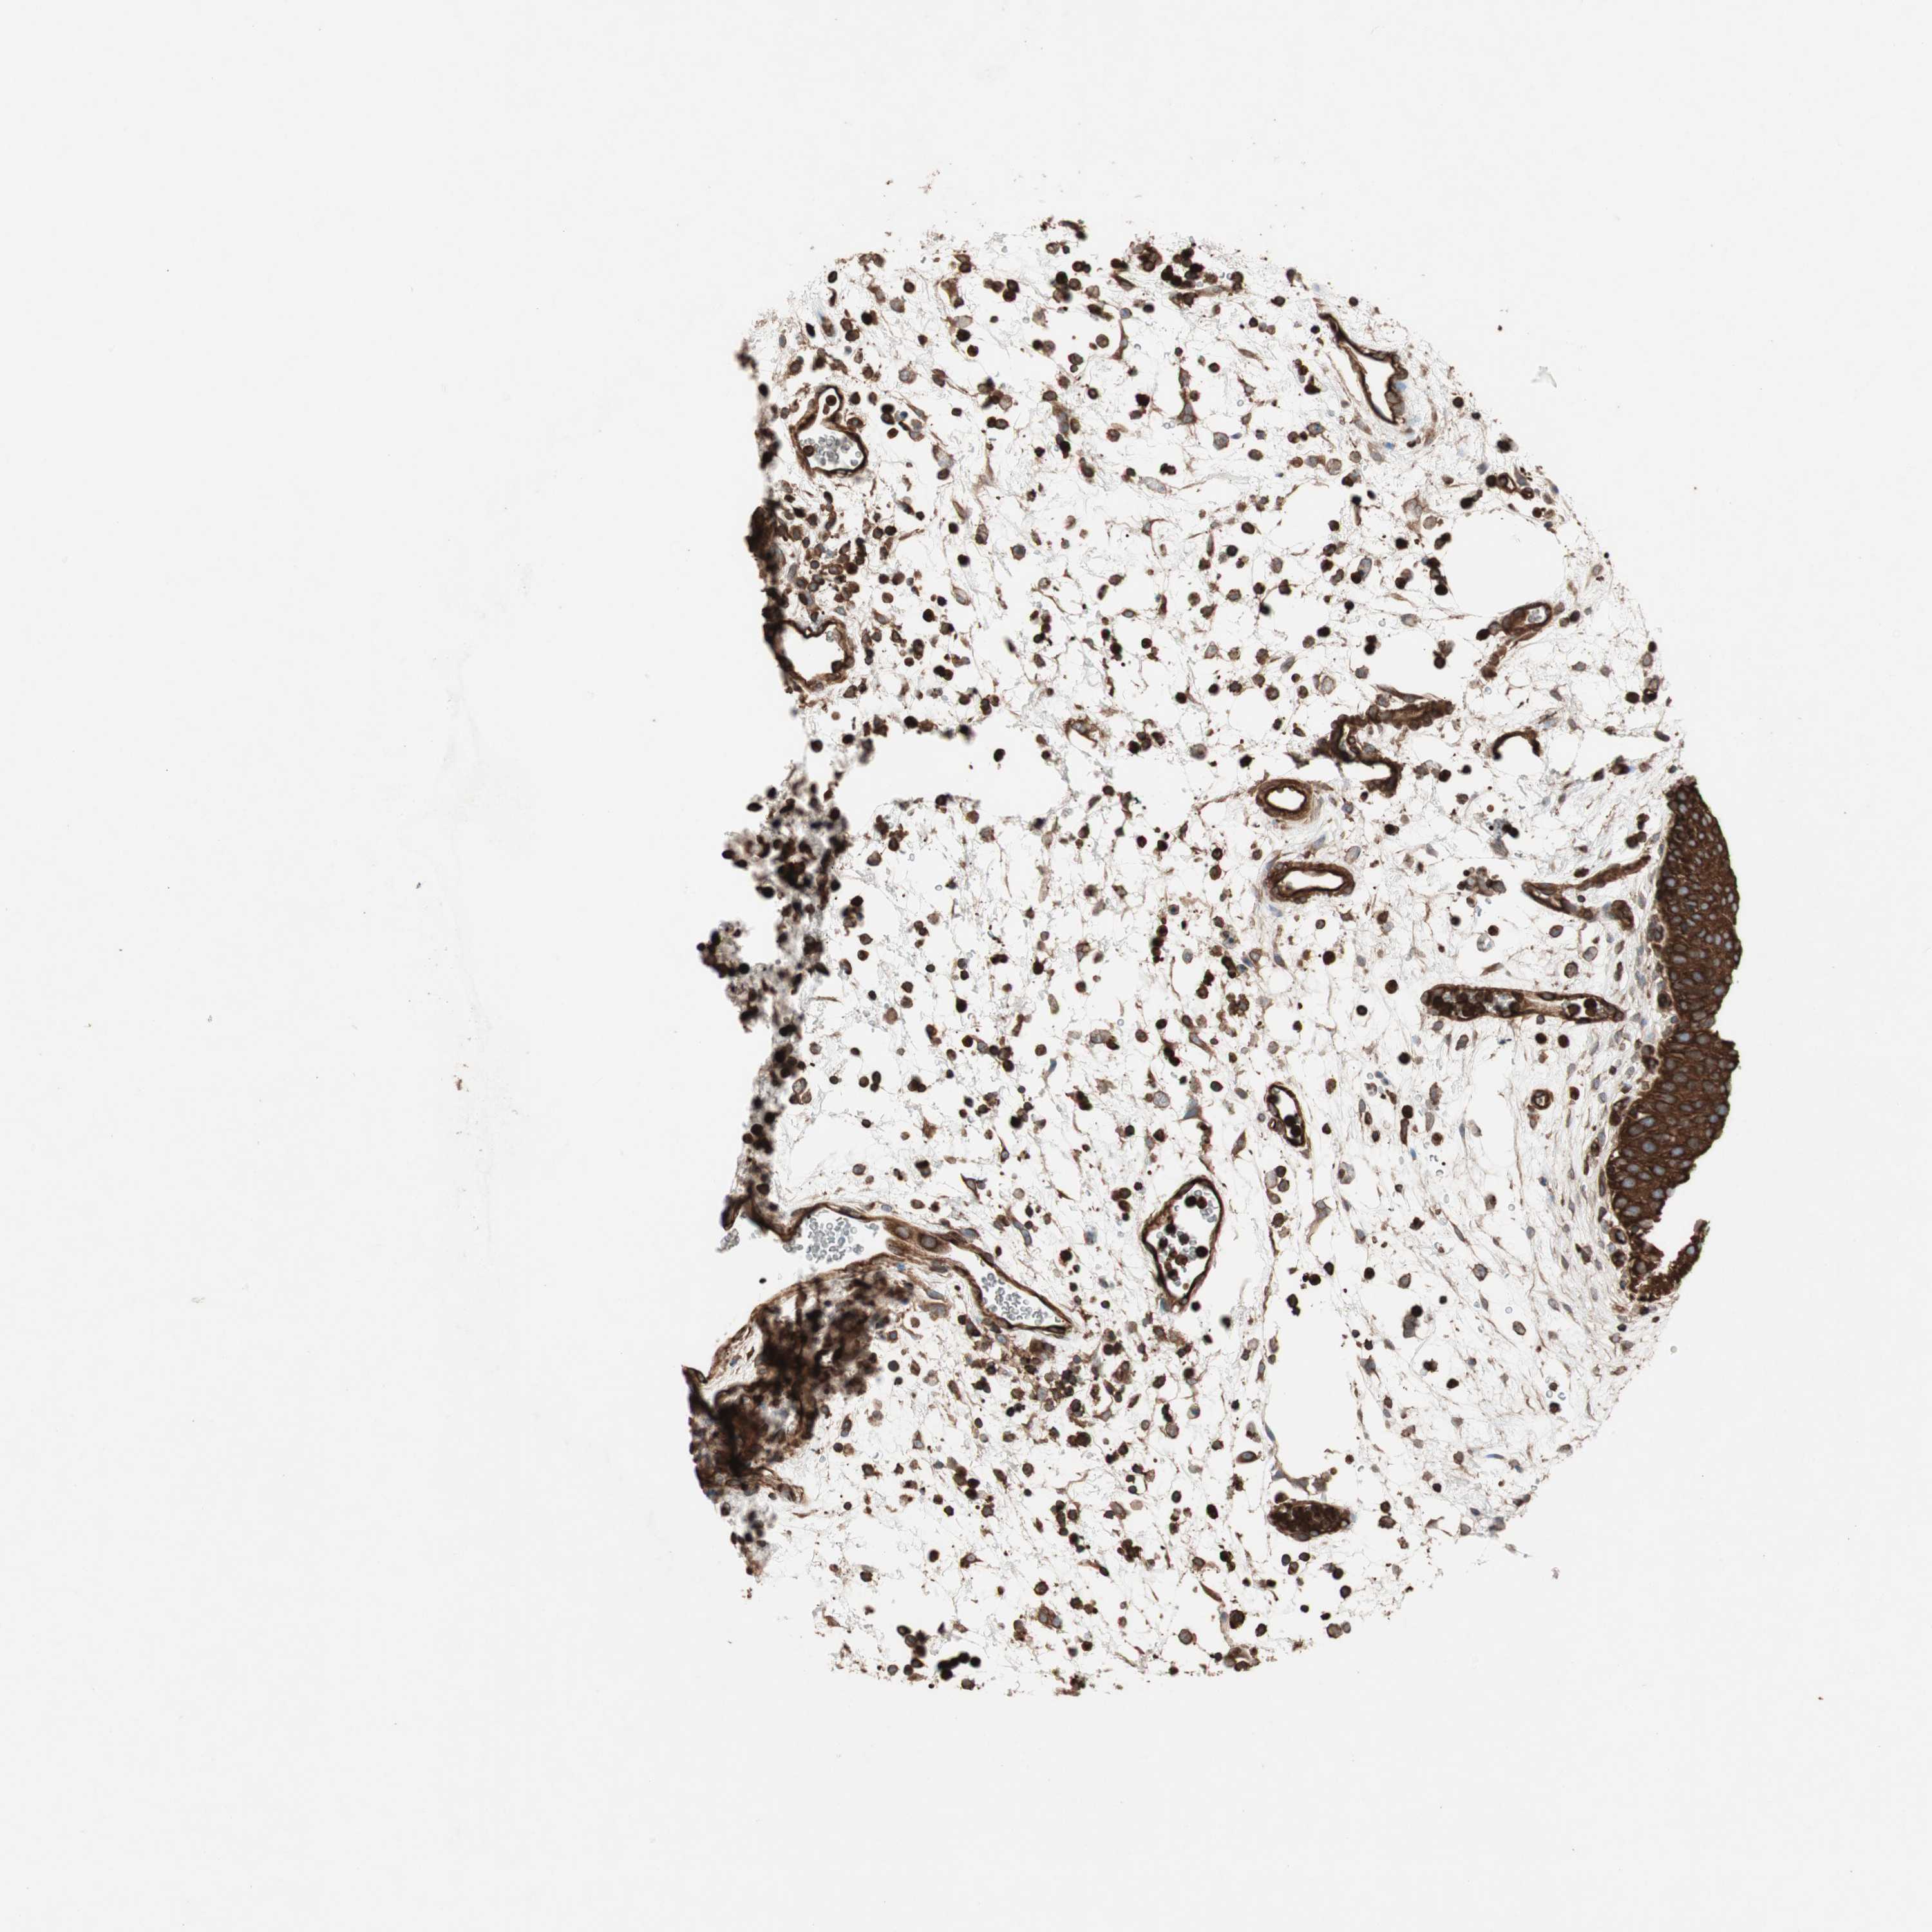

TCP11L1